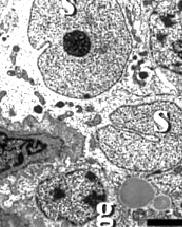

De testes produceren zaadcellen in de seminiferous tubules. Daar vind je de cellen van Sertoli (s) die de cellen voeden waaruit de spermacellen ontstaan (g). Hiernaast zie je hoe dat er bij gezonde dieren uitziet.

De clenbuterol had ook in de cellen van Leydig - de cellen in de testes die testosteron produceren - huisgehouden. Hieronder zie je Leydigcellen in een onbehandeld varken. Het rondje met een sterretje is weer een vetdruppeltje.